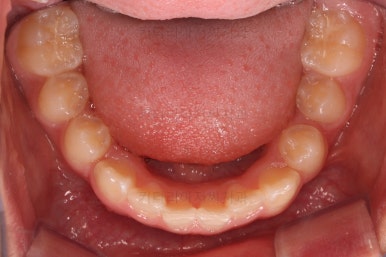

앞니의 각도가 앞으로 살아난 것이 보이실 거에요.

자연스레 과개교합 경향도 개선되어 어금니로 물렸을 때 아래 앞니가 점점 보이기 시작해요.

과개교합, 옥니, 앵글씨 2급 부정교합 모두 좋아지고 있어요.

앞니 각도가 매우 좋아졌고요.(옥니 개선) 위 아래 앞니가 덮는 정도도 개선되었어요.(과개교합, 딥바이트)

엉성했던 어금니 맞물림도 매우 좋아졌어요.(앵글씨 2급 부정교합)